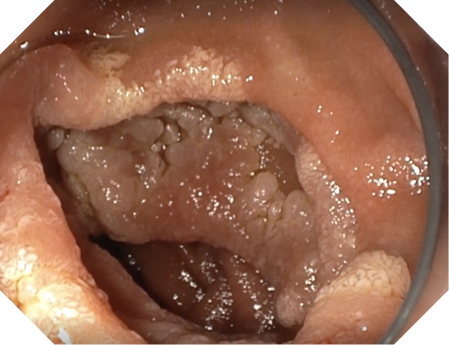

A tecnologia NBIutiliza comprimentos de onda específicos azuis e verdes que são absorvidos pela hemoglobina. A tecnologia NBIde alta definição permite a observação visual de padrões vasculares e mucosos. Durante a observação endoscópica, a tecnologia NBI™ melhora a visualização da rede capilar e da morfologia da mucosa.1

Imagens fornecidas pelo Prof. Dr. Jürgen Pohl utilizando um gastroscópio GIF-1100.